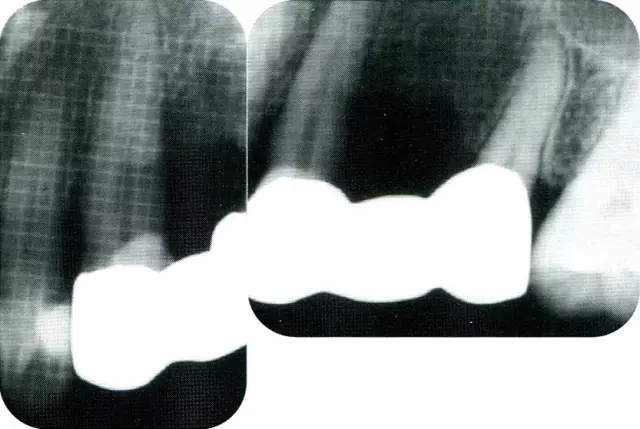

640.webp (1).jpg

▲圖7-2  術(shù)前x片。確認(rèn)存在垂直性深骨缺損。

▲圖7-7  術(shù)前,術(shù)后的x片。確認(rèn)出現(xiàn)骨再生,牙槽嵴硬線。